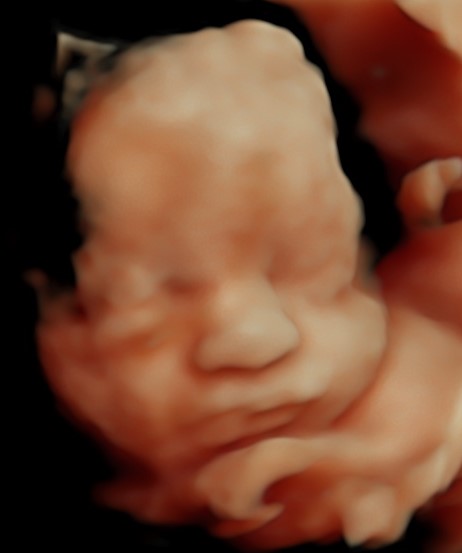

4D/5D/HD Ultrasound Gallery

Gallery